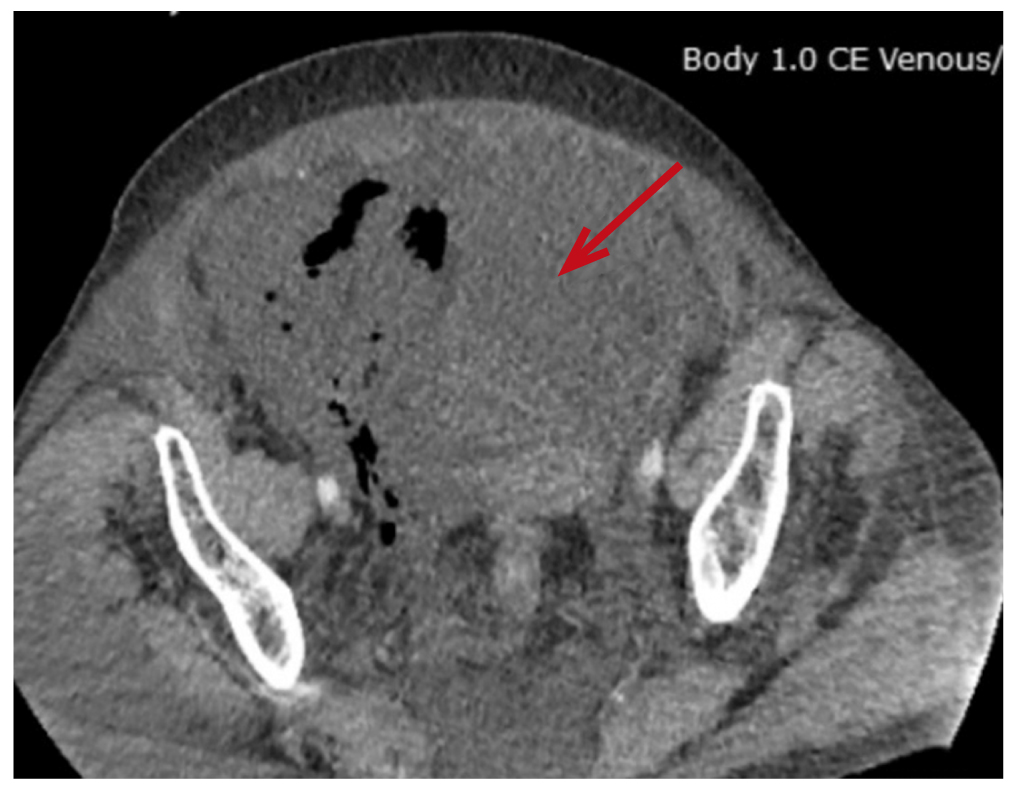

По завершении операции выполнен поворот пациентки на спину, отмечены значимое увеличение живота в объёме, тимпанический звук при перкуссии. После восстановления уровня сознания пациентка была экстубирована; предъявила жалобы на тянущие боли в области живота, позывы к мочеиспусканию, затруднение дыхания, в связи с чем направлена в отделение реанимации и интенсивной терапии (ОРИТ) для послеоперационного наблюдения и дообследования. По данным УЗИ органов брюшной полости выявлено наличие свободной жидкости. Компьютерная томография (КТ) органов брюшной полости показала наличие свободной жидкости в брюшной полости, отёк забрюшинного пространства и паранефральной клетчатки справа (рис. 4–6).

Рис. 4. Свободная жидкость в области малого таза (стрелка) по данным компьютерной томографии.

Fig. 4. Free liquid in the pelvic region (marked with arrow).